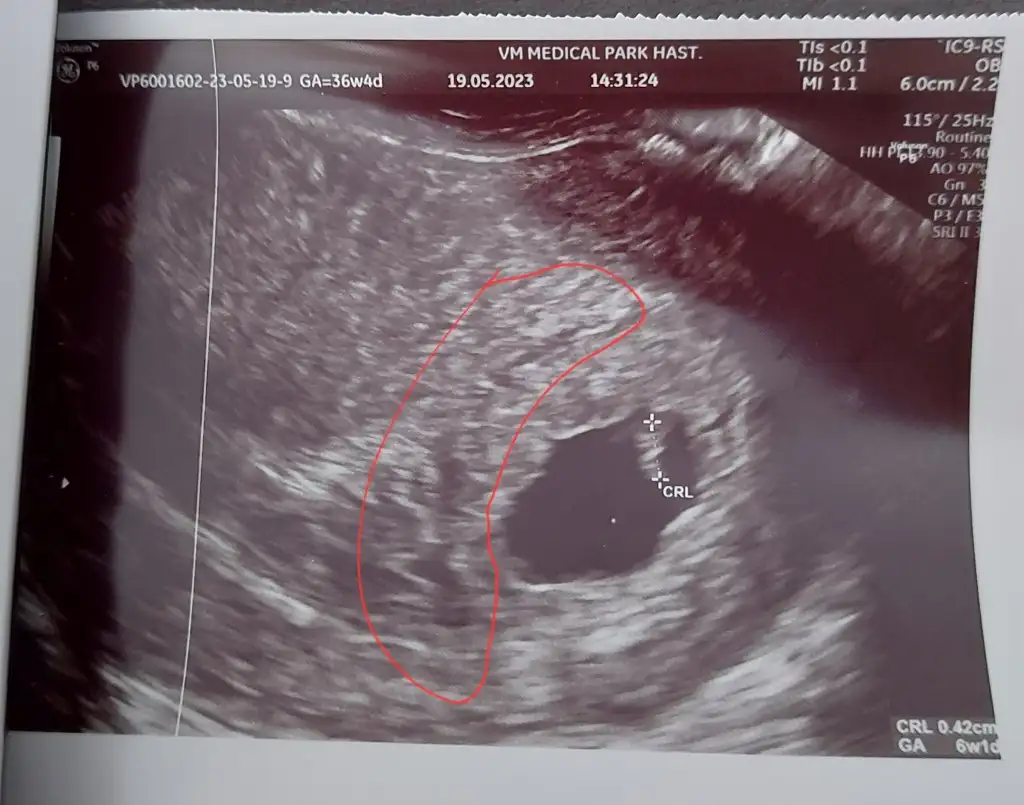

Canım ilk haftalarda olabilir korkma , ben şu an 7. Haftama girdim 6+2 de kanamam oldu kahverengi , doktora gittiğim de kendini yormuş olabilirsin az su içmiş olabilirsin dedi duphaston verdi çok şükür bitti , daha fazla dinlenmeye çalışKızlar bugün 6+6yım kese ne durumda diye doktora gittim, bu hafta hafif sızı hissediyodum ama başka sıkıntım yoktu, doktor kesenin yanında kanama gördü progestan başlıycaz. Şu işaretlediğim yerdi sanırım kanama. İnşaallah kimse yaşamasın ama eğer aynı durumu yaşayan olursa diye buraya gelişmeleri yazmak istedim.

Benimde bugün ağrım var diye gittim aynı şeyi söyledi kanama varmış fitil verdi . İnşallah kötü bir şey olmaz çok korktumKızlar bugün 6+6yım kese ne durumda diye doktora gittim, bu hafta hafif sızı hissediyodum ama başka sıkıntım yoktu, doktor kesenin yanında kanama gördü progestan başlıycaz. Şu işaretlediğim yerdi sanırım kanama. İnşaallah kimse yaşamasın ama eğer aynı durumu yaşayan olursa diye buraya gelişmeleri yazmak istedim.

İyiki erken farkedip gitmişsiniz çok geçmiş olsun bir kaç gün güzelce dinlenin Allah'ın izniyle bir şey olmaz inşallahBenimde bugün ağrım var diye gittim aynı şeyi söyledi kanama varmış fitil verdi . İnşallah kötü bir şey olmaz çok korktum